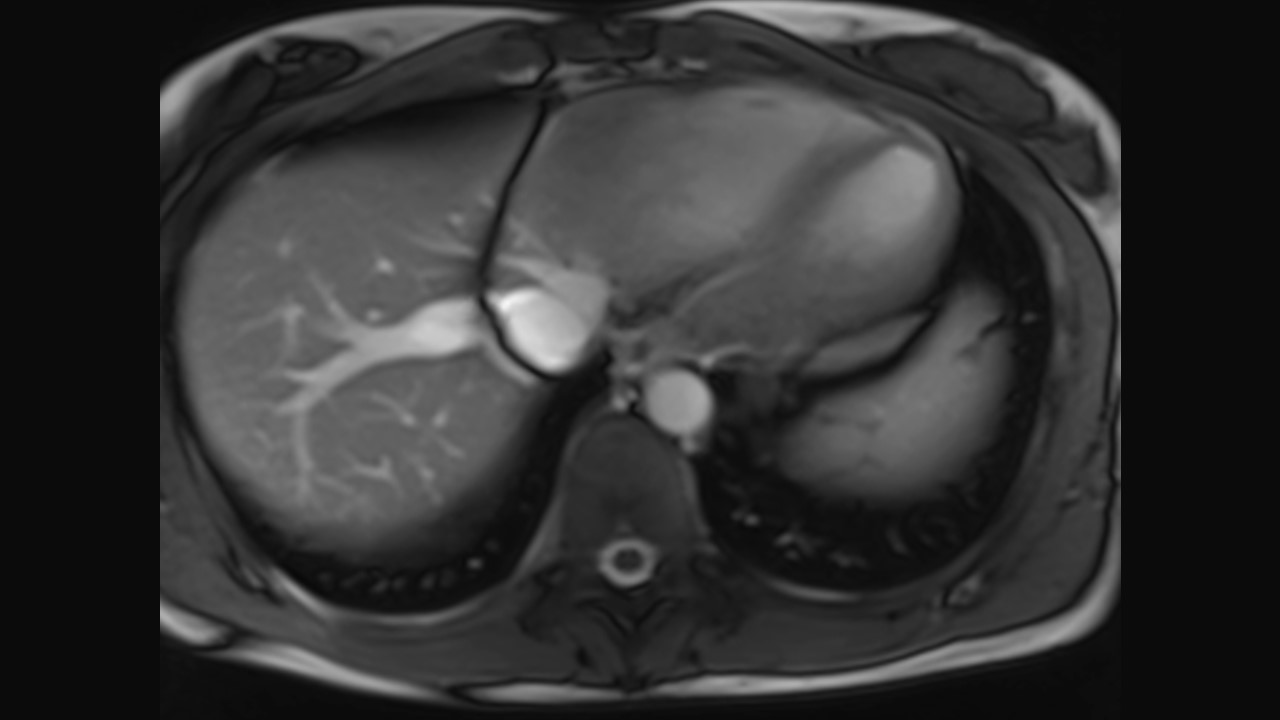

Axial Series